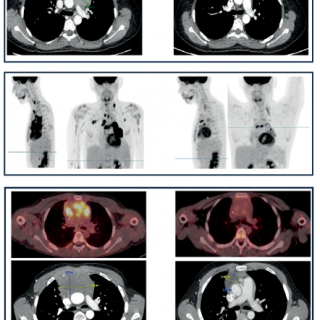

En clinique, cinq patients atteints de LAL-T ou LL-T réfractaire ont été traités avec succès : tous ont obtenu une rémission complète, permettant une greffe de cellules souches hématopoïétiques (GCSH) chez trois d’entre eux.